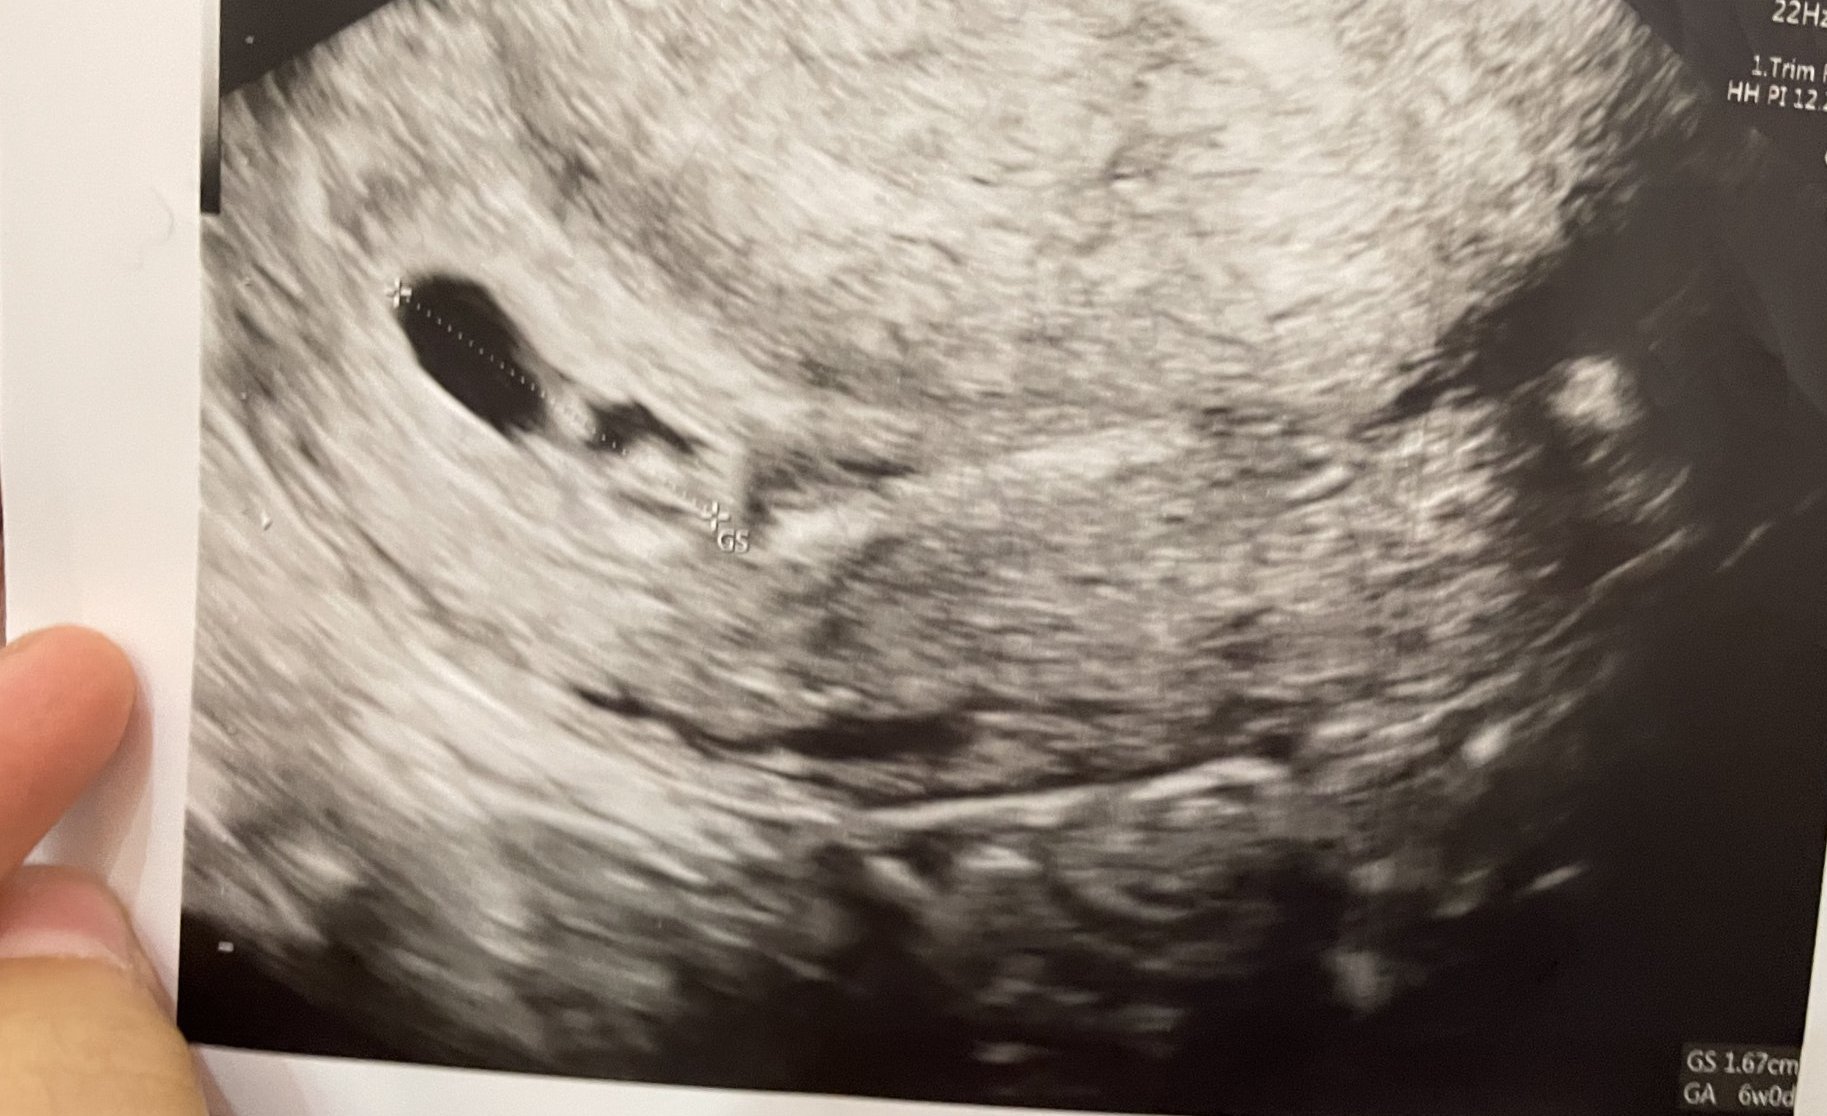

Здравейте, момичета, бихте ли ми помогнали с разчитането, направена е в 5г.с + 3 дни, доктора каза, че има жълто мехурче и пулсации, след инвитро съм, вика ме пак на 20ти, тогава ще съм точно в 7г.с, дали ще видим пулс тогава, много ми е притеснено предвид трудностите през които преминахме и не разбирам какви са размерите. Много благодаря на отзовалите се ❤️

# 434

Всичко за момента изглежда наред, щом виждате и пулсации е страхотно.

Да, би следвало в 7г.с. да чуете пулс, НО има и някои, където чуват в 8.

Успокойте се, доколкото е възможно и се насладете! Heart